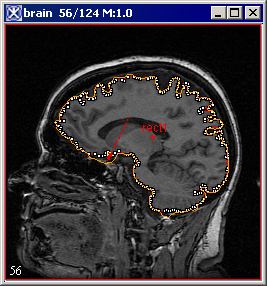

The pointer changes to the cross-hair shape. As you move the pointer, MIPAV determines the level of intensity of the pixel under the cross-hair pointer and uses the results from the Levelset algorithm to determine the probable boundary of the structure. Having determined the probable boundary, MIPAV generates a contour (Figure 1). Continue to move the pointer until the structure you wish to outline is contoured.

3 Click the contour to apply it to the structure. See Figure 1.

Figure 1. Automatically generated contour.